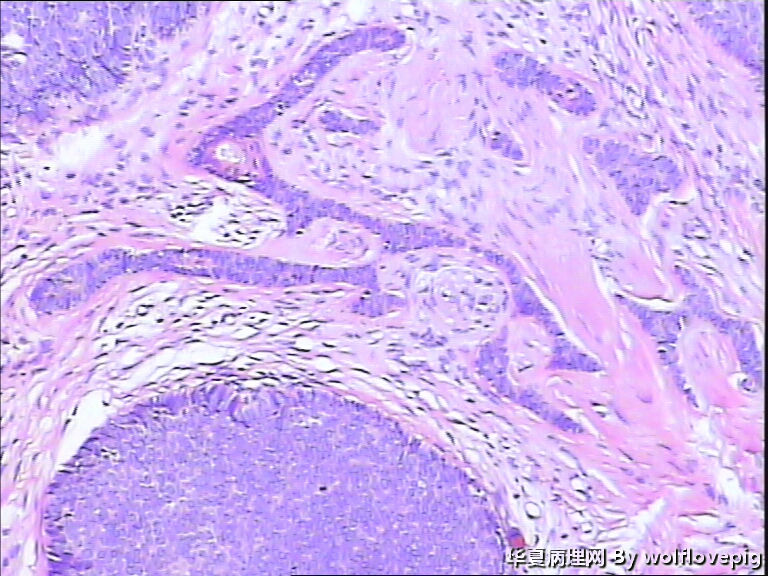

女,58y,右面部包块10年。灰白不整形带皮组织一块:2.3cm*1.5cm*0.3cm,切面有一灰白区域,质软,边界欠清。

诊断考虑毛母细胞瘤,或毛发上皮瘤。细胞团块周围可见嗜酸性纤维包绕,间质内纤维增生明显。

与表皮无关,表皮无破溃,无收缩间隙-------不支持BCC  有角囊肿 促纤维增生-----支持毛发上皮瘤